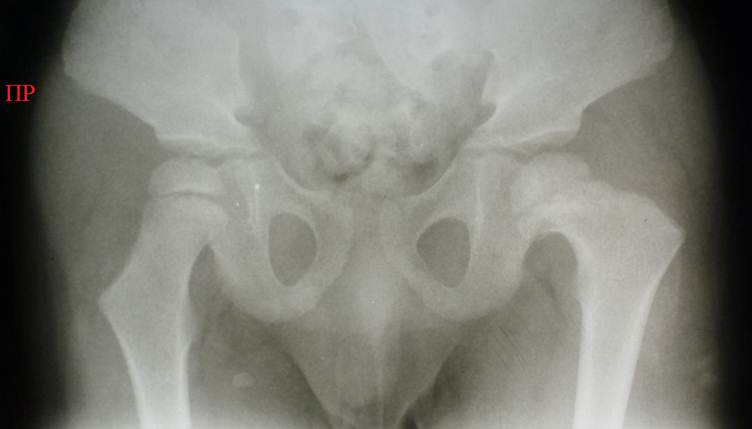

У

детей с тяжелыми формами церебрального паралича (и другими тяжелыми врожденными

заболеваниями), которые никогда не ходили, проксимальный отдел бедренной кости

значительно изменен: обнаруживается шеечно – диафизарный угол, стремящийся к

180°, и антеторсия, приближающаяся к 90°.

Снимок

таза мальчика 16 лет с тяжелой формой церебрального паралича, он никогда не

ходил. Определяется двухсторонняя Coxa Valga, стремящаяся к 180°, а также антеторсия, приближающаяся к 90° - это заметно по положению теней больших вертелов,

практически лежащих на тенях бедренной кости. Выраженный остеопороз, следы

неоднократных переломов левого бедра – результат работы «костоправов», старавшихся выпрямить

контрактуру в тазобедренном и коленном суставе.

Показатели ацетабулярной впадины справа и слева приблизительно

соответствуют возрасту 1 года, это опять же связано с тем, что ребенок никогда

не ходил. Слева имеет место децентрация головки бедра.